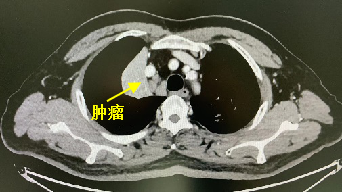

据其胸部增强CT检查显示,老秦肺部肿瘤长得十分刁钻。肿瘤有拳头大小,侵犯肺动脉、右肺上叶支气管开口,离心脏非常近(图1)。同时,也印证了肿瘤已出现纵隔淋巴结转移的情况(图2)。

图1 图2